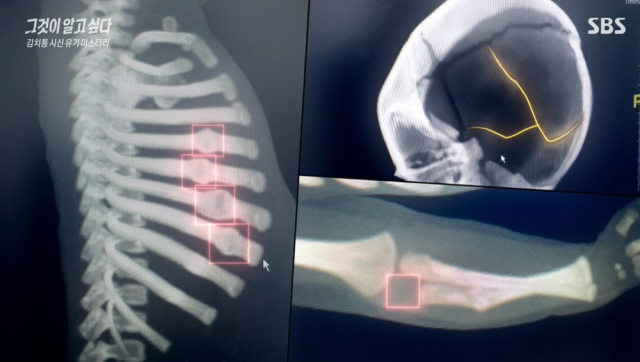

SBS ‘그것이 알고 싶다’ 캡쳐